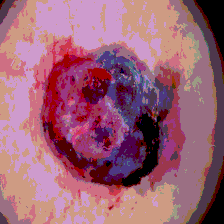

Timely identification and treatment of rapidly progressing skin cancers can significantly contribute to the preservation of patients' health and well-being. Dermoscopy, a dependable and accessible tool, plays a pivotal role in the initial stages of skin cancer detection. Consequently, the effective processing of digital dermoscopy images holds significant importance in elevating the accuracy of skin cancer diagnoses. Multilevel thresholding is a key tool in medical imaging that extracts objects within the image to facilitate its analysis. In this paper, an enhanced version of the Mud Ring Algorithm hybridized with the Whale Optimization Algorithm, named WMRA, is proposed. The proposed approach utilizes bubble-net attack and mud ring strategy to overcome stagnation in local optima and obtain optimal thresholds. The experimental results show that WMRA is powerful against a cluster of recent methods in terms of fitness, Peak Signal to Noise Ratio (PSNR), and Mean Square Error (MSE).